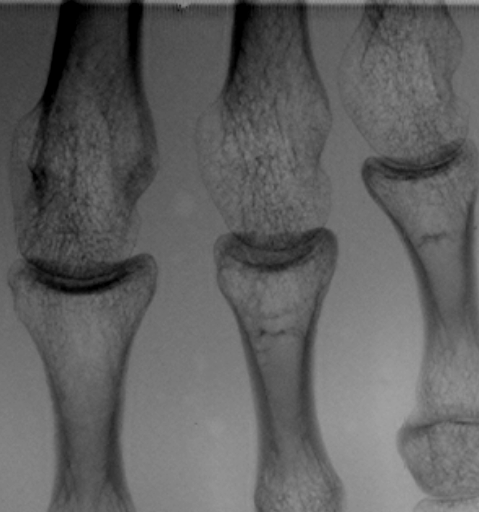

グリッド目除去は、縦方向の信号成分を

一部抜き去る処理であるため、縦方向の

骨梁の一部が消失してしまっている

ピクセル・アラインド・グリッド

(66.8本/cm,0.15mm間隔)

信号消失がまったくない